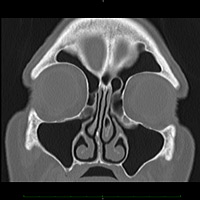

Tomografia computadorizada multi-slice (TC-MS2)

A tomografia computadorizada multi-slice (TC-MS) é um dos métodos de diagnóstico por imagem mais seguros e confiáveis actualmente. É simples, rápida e indolor. O aparelho gira os emissores de raio-x em volta do paciente fazendo radiografias transversais- do corpo, que são convertidas pelo computador, gerando as imagens digitais chamadas de 'cortes tomográficos'. A TC-MS constrói a estrutura do corpo e os órgãos internos a partir destes cortes tomográficos, possibilitando a visualização com grande precisão e confiabilidade.

As imagens geradas pela TC-MS permitem a construção tridimensional da área em estudo, tornando possível o estudo de áreas sobrepostas.